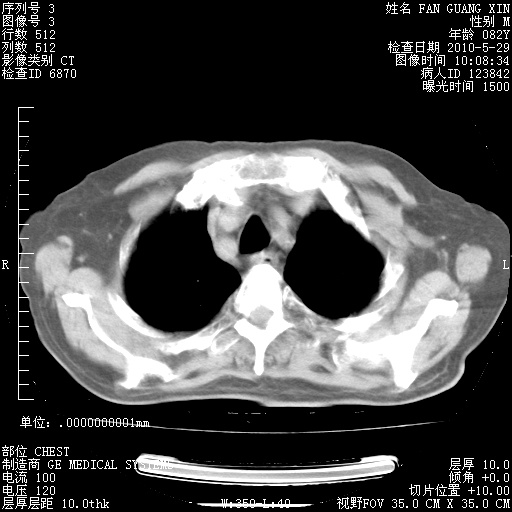

再治疗10天后的肺部CT 纵膈窗

阅读此次胸部CT,肺间质渗出性改变较入院时有吸收。目前从体温、白细胞、中性分叶明显增高,肯定存在细菌感染(发生医院感染哦,若无消化道及泌尿系统等感染的依据,肺部感染可能大)。若你院头孢哌酮舒巴坦钠耐药率较高,同意你的方案,若48小时体温仍高,可考虑使用碳青霉稀类抗菌药物,同时可予超声雾化、注意滴数时加大液体量。白蛋白33.30g/L较低哦,需加强营养等支持治疗。